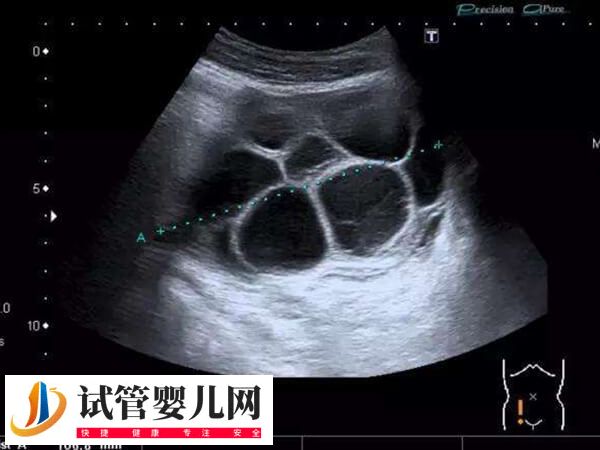

2、卵巢过度刺激综合征

取卵后卵巢过度刺激综合征,这也是导致女性在移植术后腹水的重要原因,这种病症主要是有对于促排卵药物的剂量使用把握不准,或者女性的体质较为敏感,对于卵巢刺激过度,从而诱发卵巢刺激综合征,进而导致腹水。